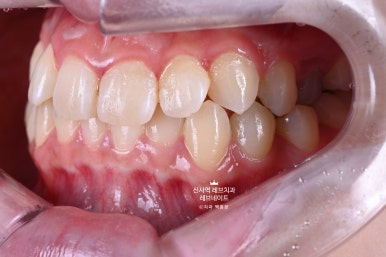

오른쪽 송곳니가 보다 안쪽에 있는 부정교합이라, 마치 치아하나가 없는 것 처럼 보이는 상태셨어요.

크라운치료를 하자니, 송곳니가 있어서 송곳니를 무조건 뽑아야 했고...

옆에서 보면 어색하지만 앞에서 보면 착시효과가 있어 치아 형태가 아주 그럴싸 해보인다는 것입니다.

뽑을까 말까 고민했던 송곳니는 뽑지 않았고,

일단 보이는 쪽에만 최대한 단단한 강도를 갖는 라미네이트로 커버해드렸습니다.